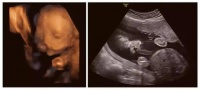

上海孕妈收好!松江妇幼超全待产包清单,涵盖妈妈护理与宝宝用品,助你精心筹备、从容迎新生!

产检可以查出脑瘤吗?备孕需警惕NF1遗传下一代